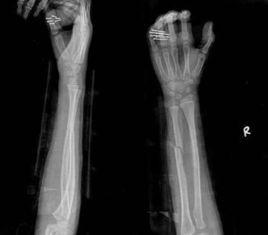

尺橈骨雙骨折切開復位內固定術

尺橈骨幹骨折常見。由於暴力的原因和受傷瞬間肢體的姿式以及肌肉收縮的狀態不同,可以發生尺橈骨幹雙骨折或單骨折。其中,又可發生於不同平面。尺骨幹上1/3骨折合併橈骨小頭脫位(孟氏骨折Montaggia fracture)。橈骨幹下1/3骨折合併下尺橈關節脫位(蓋氏骨折Galeazzi fracture)。其中尺橈骨幹雙骨折占全身骨折的5.41%,為第3位。橈骨骨折占4.23%,為第5位。尺骨骨折占1.05%,為第17位。孟氏骨折占0.63%,為第38位。蓋氏骨折占0.35%,為第50位。由於前臂具有旋轉功能,一旦發生骨折,除重疊和側方移位外,尚有嚴重的旋轉移位。因此,對復位的要求較高。如手法復位不滿意,難以達到預期功能的恢復,即有手術復位的指征。相關解剖及影像表現。

尺橈骨幹雙骨折,可以發生於同一平面,亦可發生於不同平面。內固定物的選擇應根據不同平面而定。本節介紹中1/3同一平面雙骨折,使用接骨板固定的手術步驟。為此術前應準備長四孔或短六孔接骨板或自動加壓接骨板和長度適當的螺絲釘,以及相應的工具。